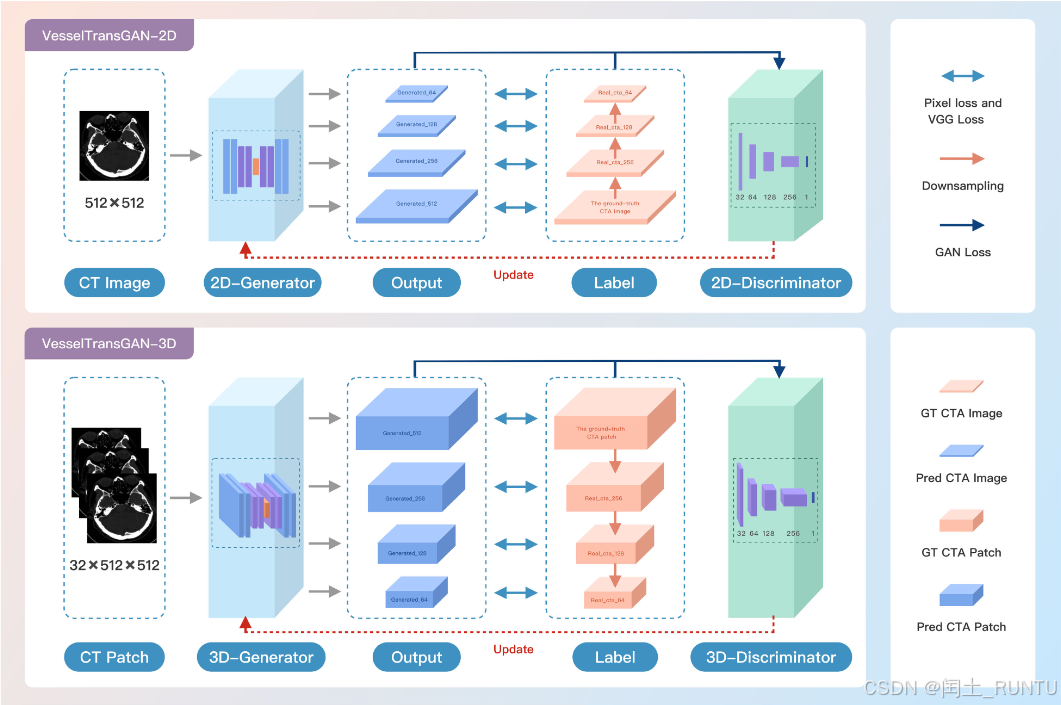

1. VesselTransGAN模型架构

文中提出了2D和3D两个子模型,最终通过提出一种2D-3D融合策略,融合两个模型的输出作为最终的生成结果。模型结构如下图所示:

由图可知,2D模型和3D模型均可输出4个不同分辨率的生成图像,而真实CTA也可通过下采样提供不同分辨率的label,用于计算GAN Loss。文中提到生成器decoder部分最后4个子模块有一个额外的ToRGB layer,用于生成不同分辨率的CTAT图像。其他细节没啥可说的。

ToRGB layer这玩意是个啥我不知道~,等以后了解了再来补充。